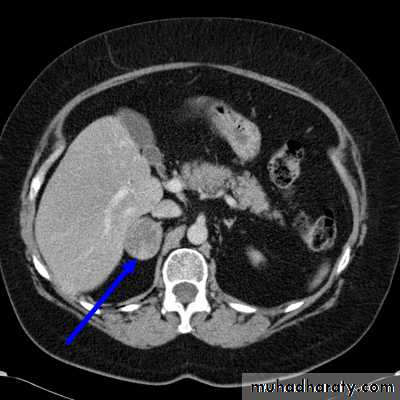

• CT of the adrenal glands is the initial investigation of choice.

• When bilateral adrenal disease is seen on CT, or when CT is normal, bilateral selective adrenal vein sampling for aldosterone levels may be helpful to localize a small abnormality and therefore guide management.